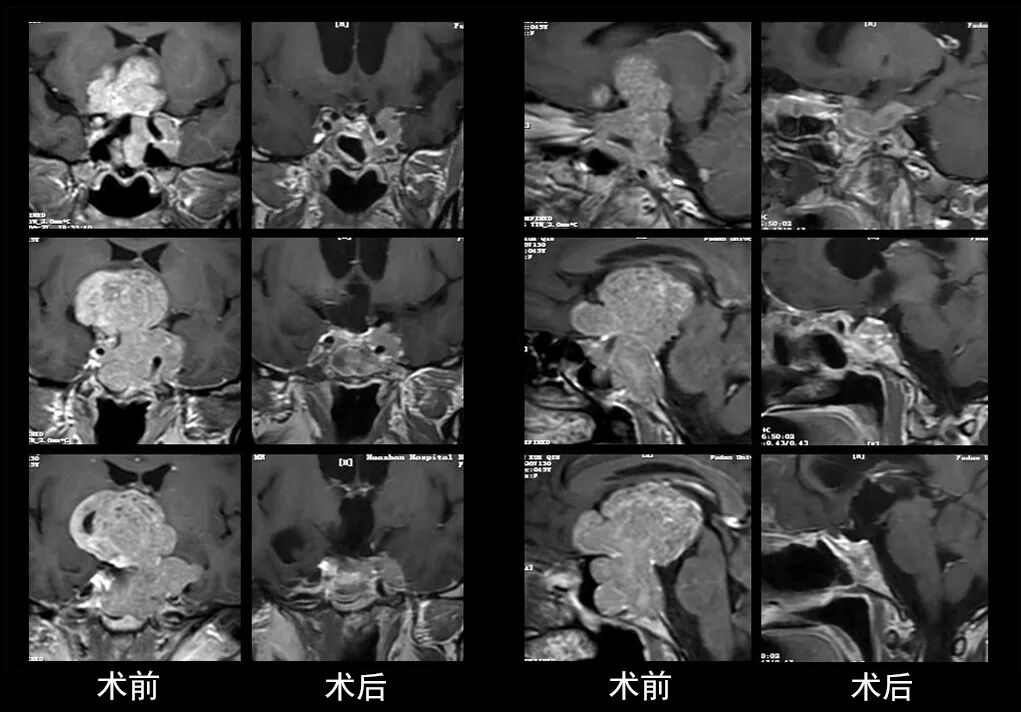

本研究中采用联合手术策略的代表性病例展示:

case 7

case 8